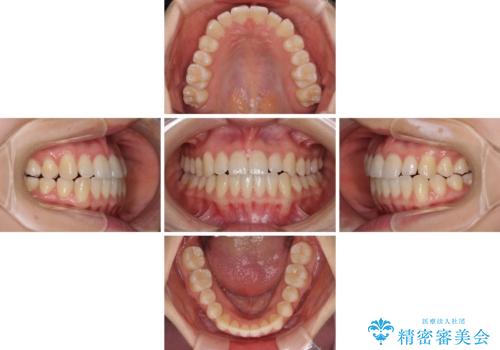

前歯のクロスバイト インビザラインによる矯正治療

- 前歯のクロスバイトを気にして来院された患者様です。

短期間での治療を希望され、ワイヤー装置とインビザラインとで悩んでいましたが、自己管理を徹底すると言うことでインビザラインによる矯正治療を行うこととしました。

しっかりとインビザラインの装着時間を守っていただいたので、1年弱で矯正治療を終えることができました。